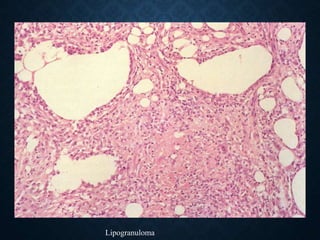

• Fat tissue necrosis - lipogranulomas

Lipogranuloma

NECROSIS AND ABSCESS

• Lipids are released from the membranes of

necrotic cells and are phagocytosed by

macrophages-lipophages

• In the focus of the abscess, fats are

released from necrotic neutrophils

• In encephalomalacia, lipids from necrotic

brain tissue, primarily myelin, are

phagocytosed by microglia-foam cells.